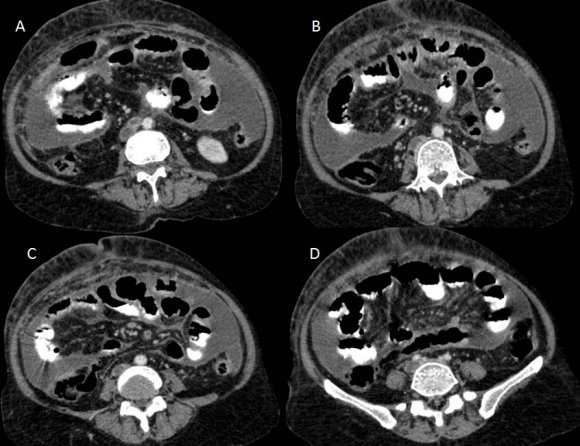

CT scan of the abdomen and pelvis (Figures: 4-8) showed changes of fatty infiltration in the liver. Multiple well-defined lymph nodes of size 1 to 2 cms were noted at portahepatis, peripancreatic region, celiac axis, left renal hilum, preaortic and para-aortic regions, precaval and paracaval regions and in right internal iliac region. Most of the lymph nodes showed peripheral enhancement with central hypodense areas of necrosis. A conglomerated matted lymph nodal mass of size 35 x 24 mm noted in the precaval region. Multiple ill-defined and nodular soft tissues infiltrate noted within the mesentery. Moderate ascites noted with mild peritoneal enhancement without septations. Ileo-caecal junction and other bowel loops appeared normal. IVC distal to renal veins showed persistent filling defect of size 10 (Anteroposterior) x 16 (Transverse) mm extending over a length of 67mm with peripheral enhancement in contrast study extending to right common iliac vein suggestive of IVC and right common iliac vein thrombosis.

Given the above findings, the possibility of tuberculous etiology with IVC thrombosis was considered.